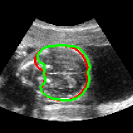

As mentioned in Sec. 3.2, it is crucial for our brain extraction network to work consistently regardless of the orientation of the brain within the US volume. This can be qualitatively observed in Fig. 3, which shows the outline of the brain-extraction prediction and the corresponding ground-truth, in red and green respectively, for six different 3D US volumes. These volumes have been selected to demonstrate the amount of variation between each scan, with the position of the fetus inside the mother as well as the position of the brain in respect to the scan varying drastically from case to case.

As shown in Fig. 3 , the network’s prediction is remarkably close to the ground-truth, regardless of the position of the brain in the volume. It also manages to accurately predict the location of the brain when this is partially obscured either by the cropping or the shape of the ultrasound beam.